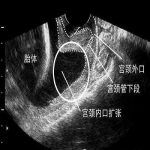

宫颈短会有什么影响?

专家指出:宫颈短,是宫颈松弛扩张的前奏,不及时埋箍,就会发展到宫口松开,胎膜早破,难免流产。

宫颈埋箍术狙击晚期流产,治疗宫颈短,宫颈松弛的最新术式。它是在3D腹腔镜下,将一个生物箍(安太环)套在宫颈内口处,能有效的阻止宫颈扩张,防止晚期流产。北京安太医院可签约治疗。